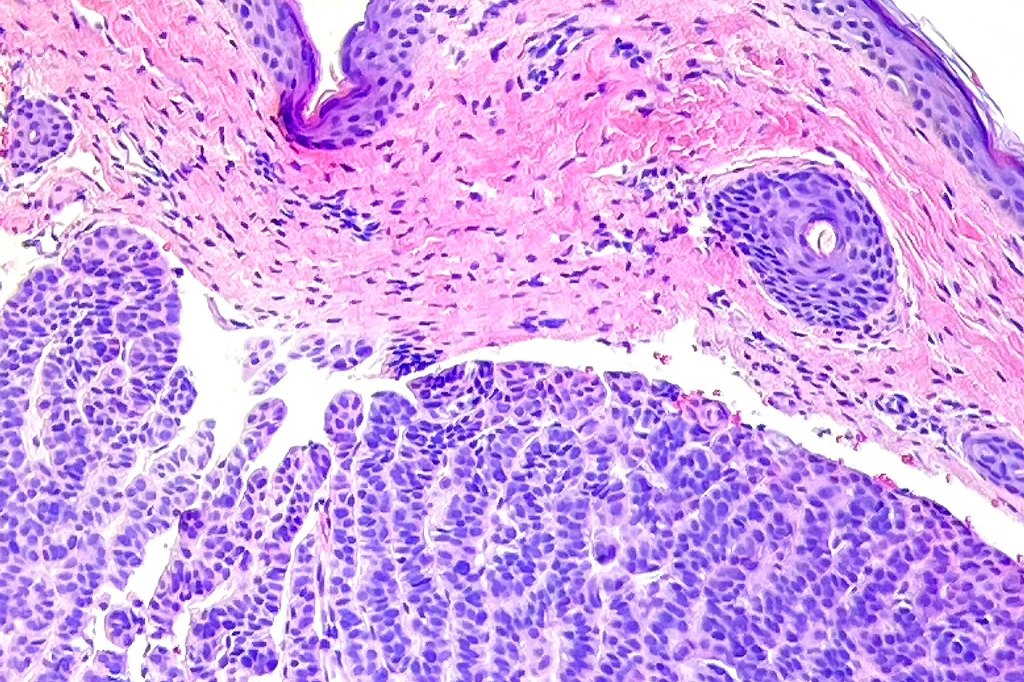

Histological features

•Variable continuity with epidermis

•Multinodular with surrounding collagenous stroma

•Random distribution of basaloid cells & sebocytes (<50% sebocytes)

•Duct formation, often with holocrine secretion generally present

•Mitoses sparse to conspicuous

•Absent peripheral palisading & retraction artifact